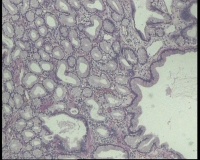

镜下见十二指肠粘液腺明显增多,排列密集,中心有少量平滑肌组织间隔,局灶腺体扩张,是十二指肠息肉还是报十二指肠腺腺瘤?